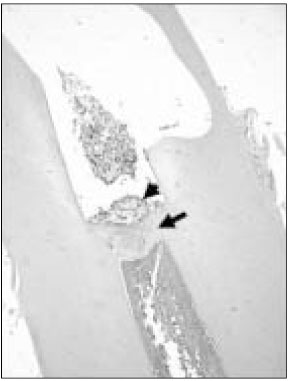

Original Article Pulp response of mineral trioxide aggregate, calcium sulfate or calcium hydroxide